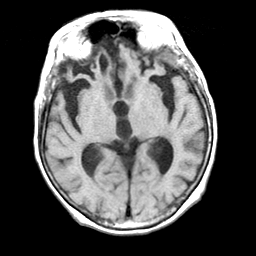

Pick's Disease, MR Study mr-t1 -- Slice #10

[Home][Help][Clinical] Slice 10